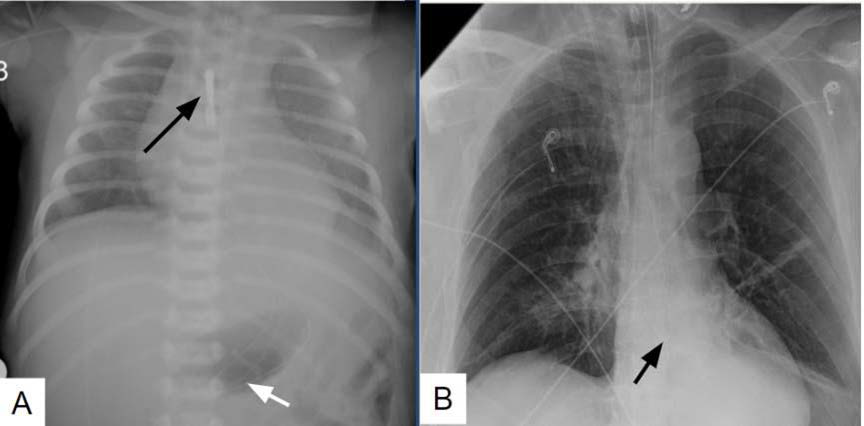

A Delayed Metastatic Storm after Molar Pregnancy: CT Chest and Brain Findings of Choriocarcinoma with Life- Threatening Hemoptysis

Mutaz Khairo, Omar Alserihy, Dania Felemban, Omima Elemam, Ahmed Elsakhawy

1-10